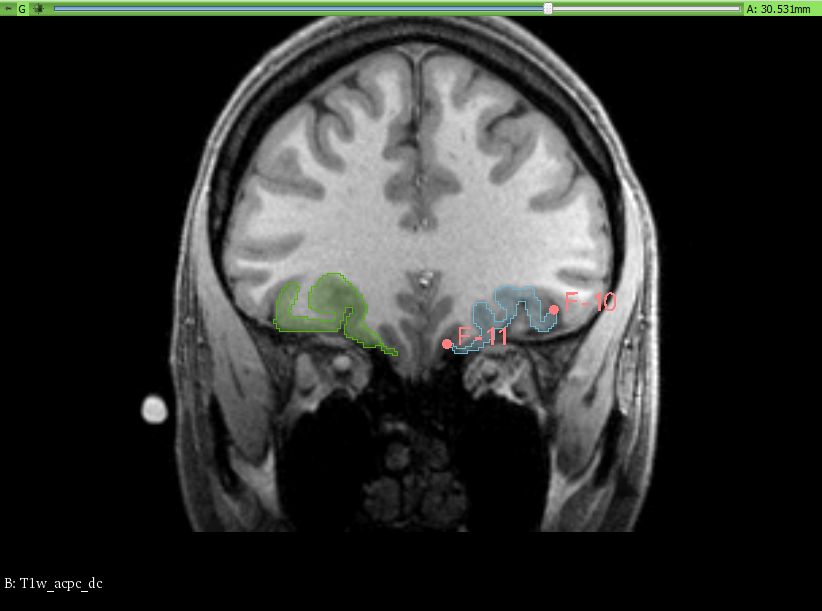

- In the OFC segment the medial and two lateral segments have been merged into a single segment. The segmentation has been done manually, tracing the contours of the desired segments between the defined anterior and posterior boundaries on the coronal view.

We have taken, for the OFC, the traditional approach, following the olfatory surcus. Fiducial points were placed on the slices for guidance.

The Slicer module used was the Segment Editor. Once the fiducial points were placed, marking the boundaries, slice by slice, the draw/paint and erase tools (with an 1 to 3% diameter) were used to manually trace and fill the corresponding areas for each segment. No other segmentation tools were used, as the work was done in an entirely manual way.

To ensure the correct overlap of the segment boundaries, when using the paint or draw tool, the setting for masking was set to editable area: outside all segments.

FreeSurfer result |

Overlap |